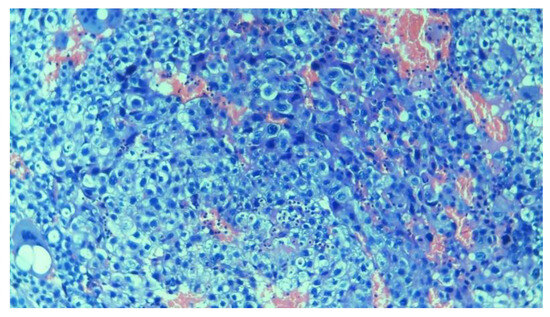

3.2.4. Trophoblastic Tissues

3.3. Baseline Models